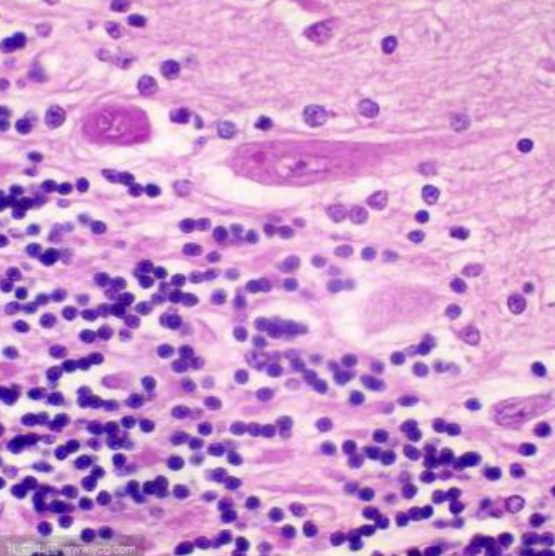

尼氏体的本质

尼氏体由粗面内质网和游离核糖体组成,富含RNA和酸性蛋白,是神经元合成功能蛋白的核心结构。其形态、分布和数量直接反映神经元功能状态:- 正常神经元:尼氏体呈块状或颗粒状,核周分布密集(如脊髓前角运动神经元)

- 受损神经元:尼氏体崩解、溶解或消失(染色质溶解现象),提示蛋白质合成受阻

- 再生神经元:尼氏体重新聚集,颗粒变细且均匀分布

染色机制

碱性染料(如焦油紫、亚甲蓝、甲苯胺蓝)通过静电作用与尼氏体内的RNA结合,形成稳定复合物。染色结果呈蓝紫色至深蓝色,细胞核浅染,背景透明。不同染料特性:染料类型 染色强度 适用场景 文献依据 焦油紫 高对比度 石蜡切片(神经元密度分析) 甲苯胺蓝 快速渗透 冰冻切片(术中快速诊断) 亚甲蓝 低背景干扰 活细胞动态观察 -

病理学意义

- 退行性疾病:阿尔茨海默病中皮层神经元尼氏体减少,与Tau蛋白磷酸化相关

- 缺血性损伤:脑缺血30分钟后海马CA1区尼氏体溶解,提示不可逆损伤

- 轴突反应:周围神经损伤后,背根神经节神经元尼氏体重新分布(中央染色质溶解)